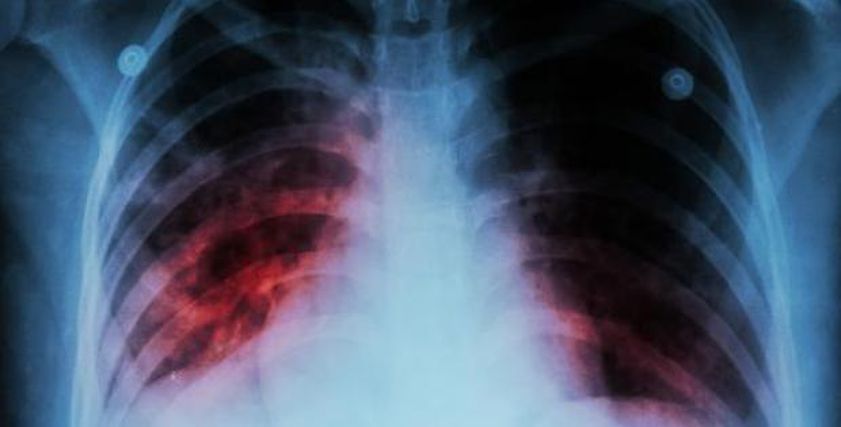

وكشفت أن الأعراض الرئيسية للدرن، تشمل السعال المستمر لأكثر من أسبوعين، فقدان الوزن غير المبرر، التعرق الليلي، والتعب المزمن، مشيرة إلى أن التشخيص يتم عبر اختبارات مثل فحص الجلد، تحليل البلغم، والتصوير بالأشعة السينية.